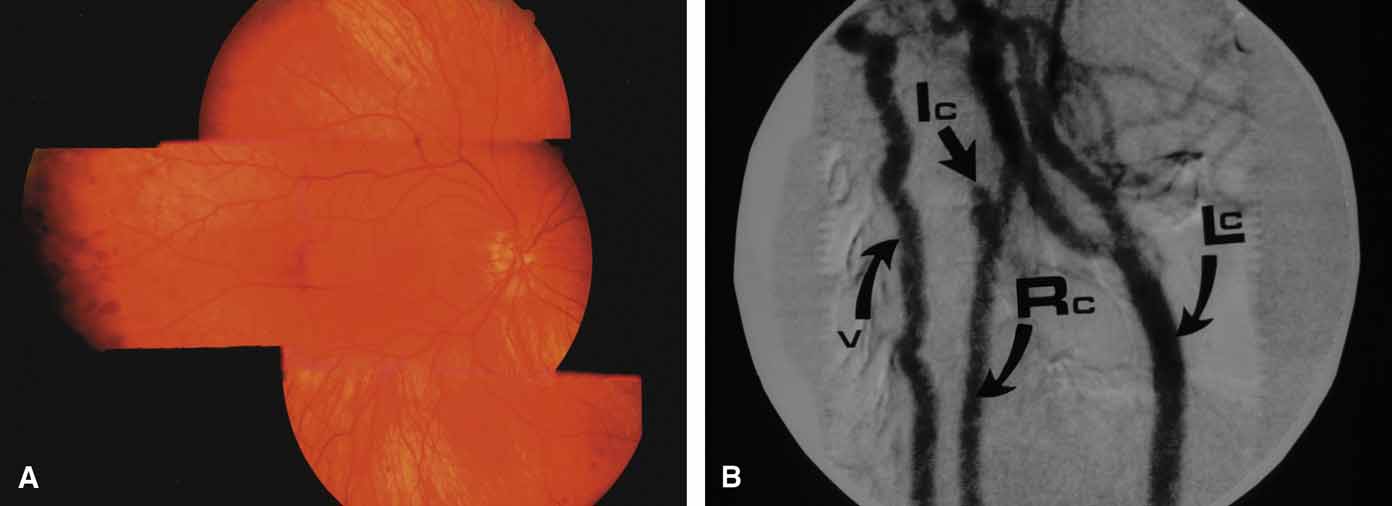

Features of ocular ischemia including neovascular glaucoma may develop when severe carotid occlusive disease results in hypoperfusion. A dot-blot peripheral retinopathy with microaneurysms (venous stasis retinopathy of Kearns) may be present in 5% of patients with established carotid artery stenosis of greater than 70% flow reduction (Fig. 26). However, iris neovascularization and glaucoma may develop in the absence of posterior segment manifestations148 and make the underlying carotid pathology difficult to diagnose. Since the ciliary body is subject to both hypoxia and hypoperfusion, neovascular glaucoma may be normotensive or even hypotensive.149 Endarterectomy may improve flow and may transiently lead to regression of iris neovascularization and lowering of pressure elevation. When neovascularization of the angle results in increased intraocular pressure, then panretinal photocoagulation is indicated. Other cycloablative methods, such as transscleral diode laser cyclophotocoagulation therapy or continuous wave transscleral Nd: YAG ablation, may be considered when panretinal photocoagulation fails or is not possible.

Fig. 26 Venous stasis retinopathy of carotid artery disease. A. Mid-peripheral dot-blot hemorrhages and microaneurysms in asymptomatic patient with right carotid obstruction. B. Digital subtraction angiogram, venous method, showing complete right internal carotid obstruction (Ic) (v, vertebral; Ic, internal carotid; Rc, right common carotid; Lc, left common carotid).